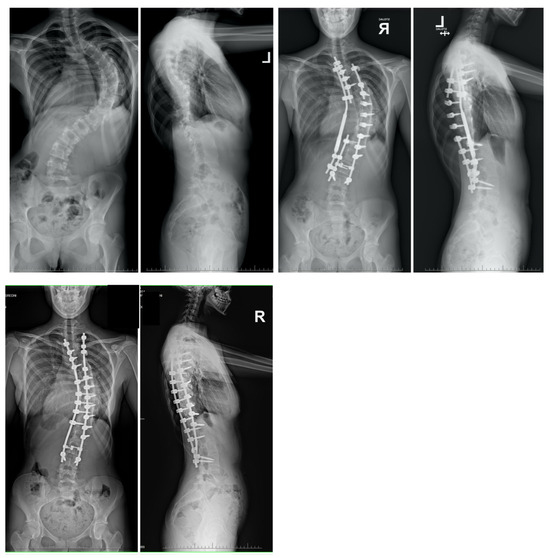

10. Rib Resection/Thoracoplasty

11. Author’s Preferred Technique